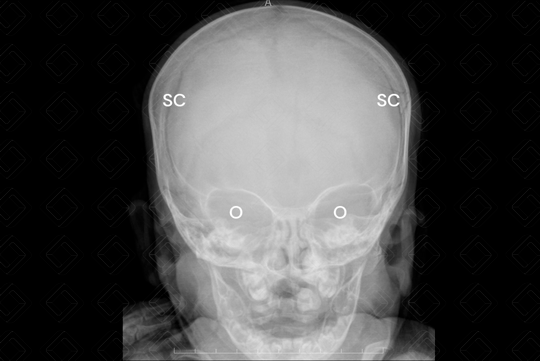

Radiografia de crânio AP e perfil (são as incidências padrões realizadas neste exame).

Legenda: SC = sutura coronal; SL = sutura lambdoide; O = órbita.